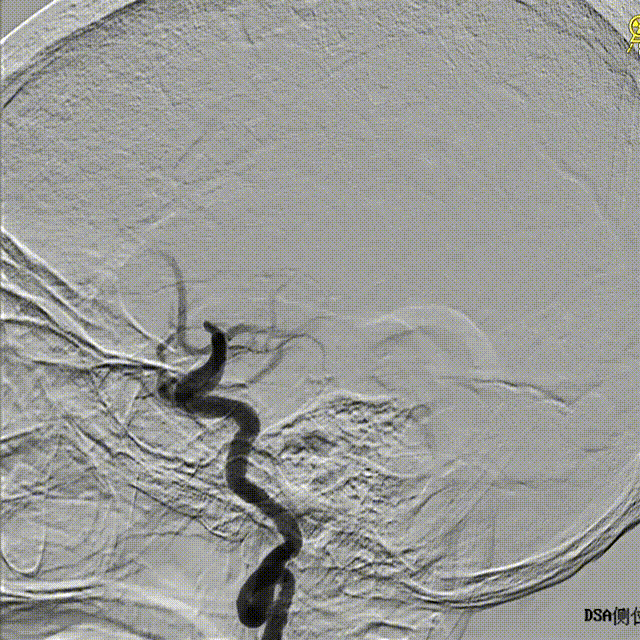

术后正侧位造影

正位

侧位